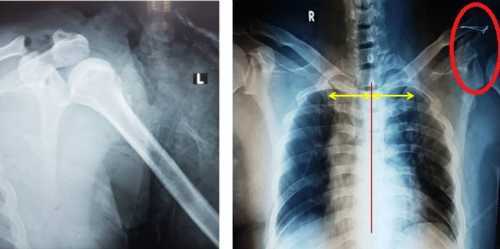

Anh Vương Phùng Thảo (48 tuổi) trong lúc đi bộ bị đuôi xe tải đập vào vai trái làm biến dạng cẳng tay.